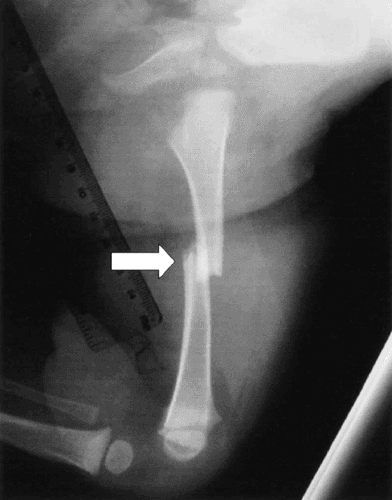

Pathological Fracture - आजारामुळे हाडे कमजोर होऊन तुटणे.